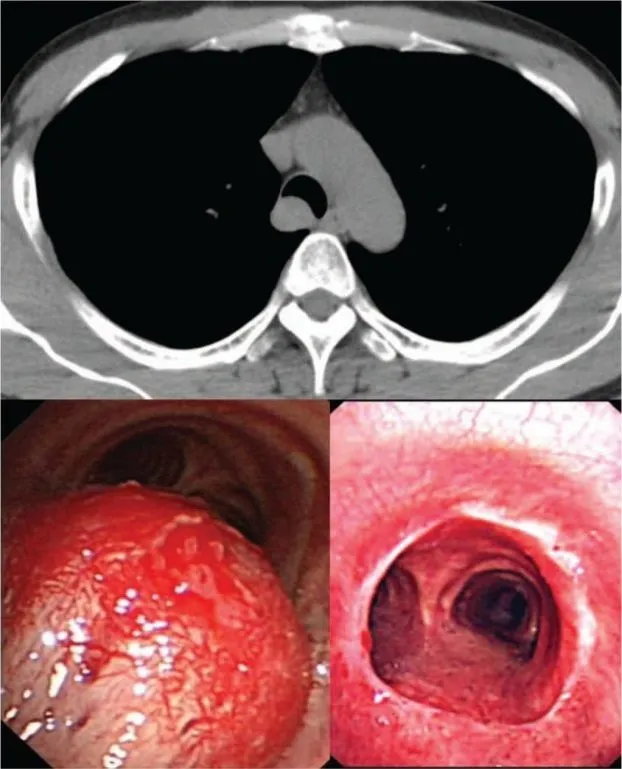

Что такое рак трахеи . Раковые новообразования в трахее развиваются нечасто . Они чаще встречаются у лиц мужского пола, чем у женщин, в 40-60 лет . У детей опухоли в большинстве (90%) случаев являются доброкачественными . Рак трахеи (код по Мкб10 — C33) обычно локализуется в нижнем . . .

Рак трахеи . Рак трахеи - достаточно редкое онкологическое заболевание, может быть первичным и вторичным . Первичный рак трахеи - злокачественный процесс начинается непосредственно в клетках органа, вторичный - результат прорастания/распространения опухоли из . . .

Плоскоклеточный рак трахеи, в отличие от такого же рака лёгкого, чуть менее злобный с не такими бурными темпами роста .